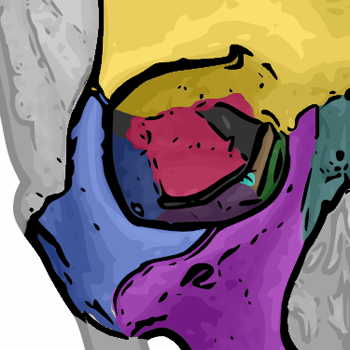

Das Auge ist in der knöchernen Augenhöhle, auch Orbita genannt, eingefasst(4). Diese ist eine nahezu viereckige pyramidenförmige Höhlung im Frontalbereich des Schädels (2). Sie hat ein Volumen von etwa 30 ml von denen 7 ml vom Augapfel selbst eingenommen werden. Da der Schädel eines Menschen aus mehreren getrennten Knochen besteht, welche im Laufe des Heranwachsens zu einem festen Knochen zusammenwachsen (TODO: QUELLE für mehr Infos: https://flexikon.doccheck.com/de/Sch%C3%A4delknochen ## 5. Schädelwachstum), bildet sich die Augenhöhle aus Anteilen von insgesamt sieben verschiedenen Knochen (2). In Abbildung XY sind diese Knochen farbig dargestellt und benannt. Die sieben Knochen sind:

- Jochbein (Os zygomaticum) in blau

- Stirnbein (Os frontale) in gelb

- Tränenbein (Os lacrimale) in grün

- Oberkiefer (Maxilla) in violett

- Siebbein (Os ethmoidale) in braun

- ein kleiner Teil des Gaumenbeins (Os palatinum) in hellblau

- Keilbein (Os sphenoidale) in rot

! Quelle: Wikipedia

Dabei wird die Augenhöhle in vier Begrenzungen einteilen: Das Orbitadach bildet die obere und hintere Begrenzung der Augenhöhle und wird vom Stirnbein (gelb) und Keilbein (rot) gebildet. Der Orbitaboden begrenzt die Augenhöhle nach unten und besteht hauptsächlich aus dem Oberkiefer (violett) und teilweise aus dem Jochbein (blau). Die laterale Orbitawand begrenz die Augenhöhle von der Körpermitte aus gesehen nach außen (links bzw. rechts). Sie wird vor allem aus dem Jochbein (blau) und teilweise aus dem Keilbein (rot) gebildet. Zuletzt begrenzt die sehr dünne mediale Orbitawand die Augenhöhle zur Körpermittel bzw. Nase hin und wird aus dem Oberkiefer (violett), dem Tränenbein (grün), dem Siebbein (braun) und Teilen des Stirnbeins (gelb) sowie des Keilbeins (rot) gebildet.

Abbildung XYZ zeigt eine Frontalansicht der Augenhöhle. Dort sind der Orbitarand und die Knochen, die ihn bilden eingezeichnet. Analog zu den Begrenzungen der Augenhöhle, gibt es den oberen Orbitarand, der hauptsächlich durch das Stirnbein (gelb) gebildet wird. Der laterale (also äußere) Orbitarand wird durch das Jochbein gebildet. Der untere Orbitarand wird durch Teile des des Jochbeins sowie des Oberkiefers gebildet. Der mediale Orbitarand besteht aus Teilen des Stirnbeins sowie dem Tränenbein und Oberkiefer.

Der Orbitalrand wird durch das Stirnbein (gelb), das Jochbein (blau) und den Oberkieferknochen (violett) gebildet. Im Vergleich zu den Orbitalbegrenzungen ist er relativ robust, da er das Auge vor äußeren Einwirkungen schützen muss (2).